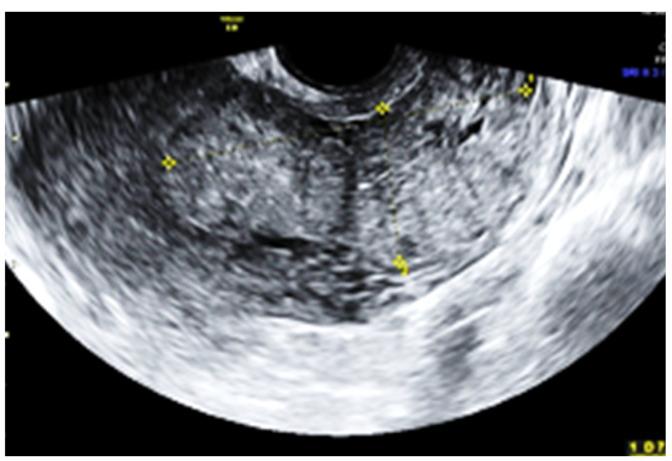

Placental morbid adherence is a known risk factor for postpartum hemorrhage. The incidence of abnormal placental attachment has been increasing over the past few decades, mainly due to rising rates of cesarean deliveries, advanced maternal age, and the use of assisted reproductive technologies. Cesarean section is a significant risk factor for placenta increta, as it disrupts the normal architecture of the uterine wall, making it more difficult for the placenta to detach after delivery. We present the case of a woman who underwent a cesarean section at 28 weeks due to anterior placenta previa, accompanied by hemorrhage and rupture of membranes. Following the delivery, she experienced normal postoperative bleeding and was discharged home after five days. However, six weeks later, she presented with heavy bleeding, leading to the decision to perform a total hysterectomy. The levels of HCG were found to be low. The pathological examination of the specimens confirmed a diagnosis of placenta increta, as it revealed notable placental proliferation, necrotic villi, and placental invasion near the uterine serosa. Notably, we did not find any similar cases documented in the literature. Patients experiencing prolonged vaginal bleeding after childbirth and diagnosed with placenta accreta should be closely monitored through ultrasound examinations; abnormal proliferation of the placenta can occur, and prompt detection is crucial for appropriate management.

胎盘植入是产后出血的已知危险因素。在过去几十年中,异常胎盘附着的发生率一直在上升,主要是由于剖宫产率上升、产妇年龄增大以及辅助生殖技术的使用。剖宫产是胎盘植入的一个重要危险因素,因为它破坏了子宫壁的正常结构,使得胎盘在分娩后更难剥离。我们报告一例因前置胎盘于孕28周行剖宫产的妇女病例,术中伴有出血和胎膜破裂。分娩后,她术后出血正常,五天后出院。然而,六周后,她出现大量出血,遂决定行全子宫切除术。发现血HCG水平较低。标本的病理检查证实为胎盘植入,因为它显示出明显的胎盘增生、坏死绒毛以及子宫浆膜附近的胎盘侵入。值得注意的是,我们在文献中未发现任何类似病例的记载。产后出现长时间阴道出血且诊断为胎盘植入的患者应通过超声检查密切监测;胎盘可能会出现异常增生,及时发现对于恰当的处理至关重要。